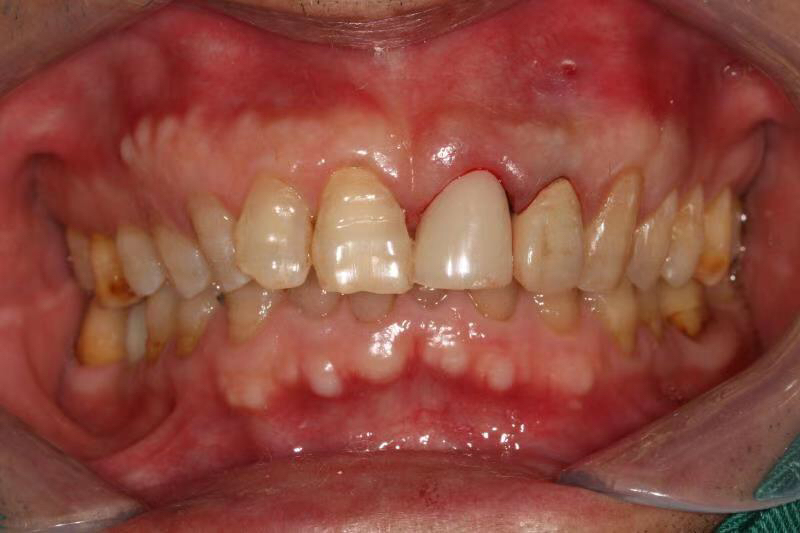

患者中年男性,左上中切牙外院烤瓷冠修复多年,因牙冠脱落前来就诊,由于牙冠制作不够密合,牙齿已经腐烂成残根,无法修复,只能进行种植修复,由于是门牙,我们在做完种植术后为患者制作了临时冠,最大程度保证了美观性。